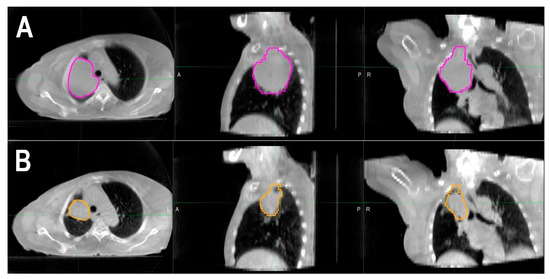

2.2. Tumor Regression